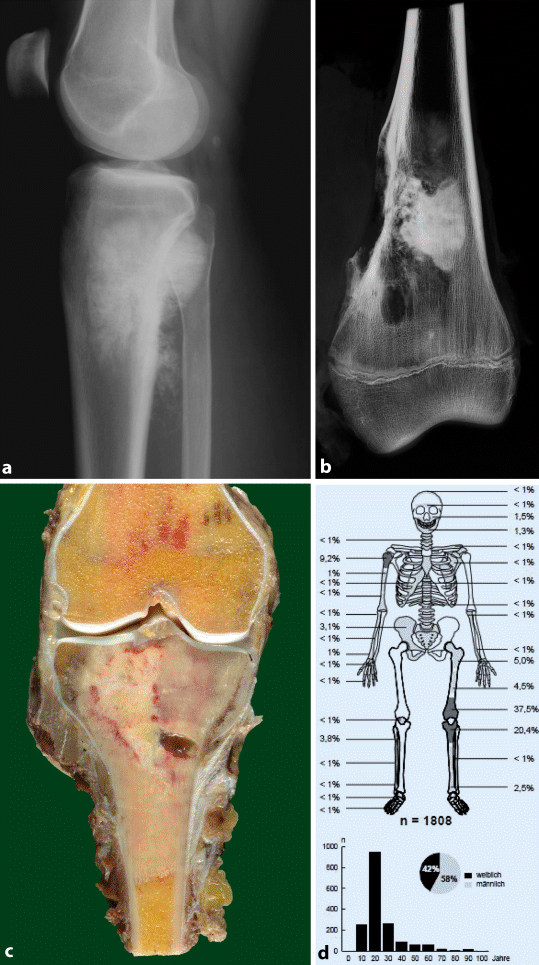

Osteolyse Wikipedia